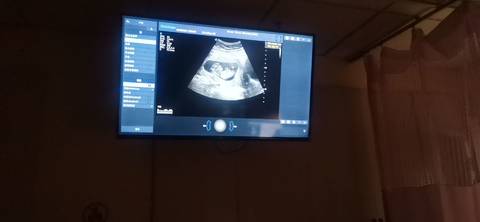

请问是男孩女孩,能看出来吗

二十周左右去看比较准

你好。我们是判断不了男宝宝跟女宝宝的,孕期定期检查,我觉得宝宝健康就好的。祝心想事成 。

你好根据B超单子是看不出男女的只要宝宝健康才是我们最大的心愿不是吗?最后祝宝妈心想事成哦。

你好,对于宝宝是男孩女孩虽然很好奇,但是怀孕的单子、数据、表现是判断不出来的,在这也愿你心想事成。

听说可以从心率判断